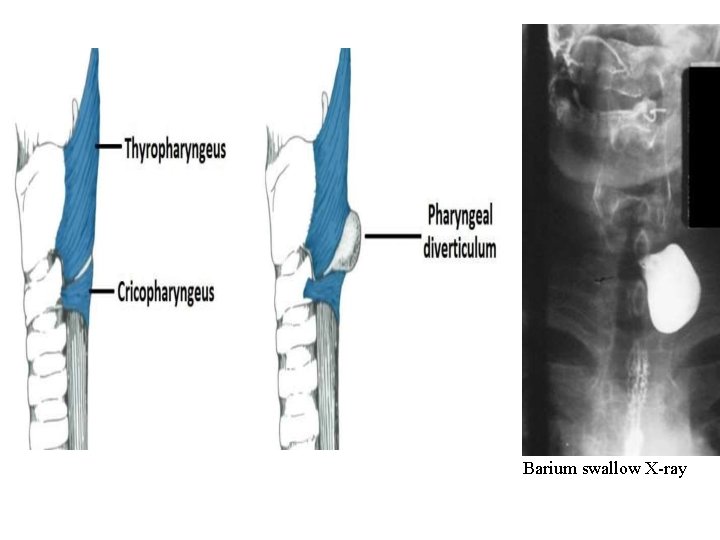

Clinical Relevance: Pharyngeal Diverticulum (Pouch) Inferior pharyngeal constrictor is found in the laryngopharynx and has two components. The superior component (cartilage and the inferior component (cricopharyngeus) has horizontal fibres that attach to the cricoid cartilage This area between the two is a weak area in the muscosa. Normally during swallowing, the thryopharyngeus contracts as the cricopharyngeus relaxes, allowing the bolus of food to be propelled into the oesophagus and preventing the intrapharyngeal pressure form rising. If this coordinated relaxation of the cricopharyngeus does not occur, the intrapharyngeal pressure tends to rise and pharyngeal mucosa forms a midline diverticulum in the area between the thyropharyngeus and cricopharyngeus. It is possible for food to accumulate here, leading to dysphagia.

Barium swallow X-ray